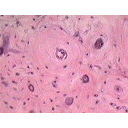

ostéons.jpg